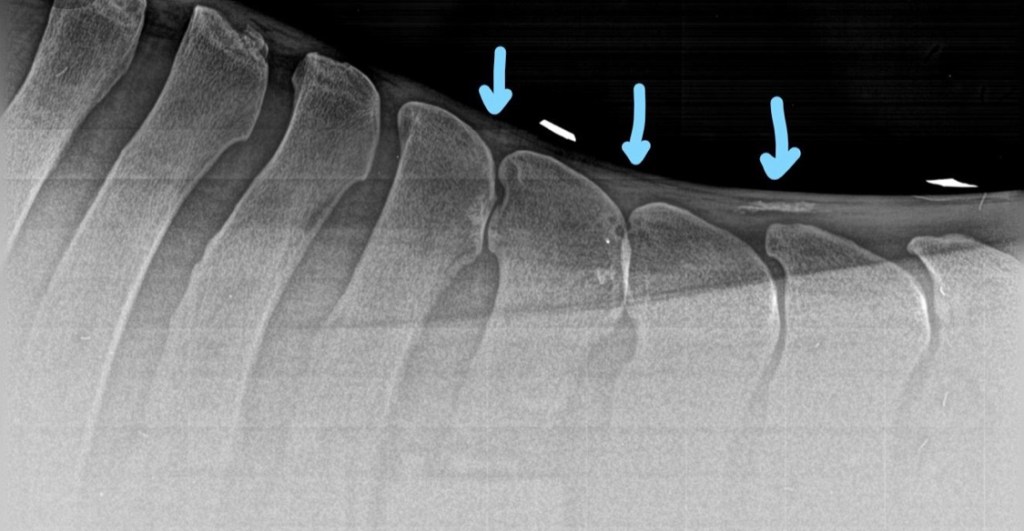

The locations and number of vertebrae involved can vary. Kissing spines most commonly occur between thoracic vertebrae (T) 13 and 18, with T15 the most often affected. This is the site where the angle of the dorsal spinal process changes orientation. It is also the site directly under the saddle and the rider’s seat. Kissing spines have also been observed in the lumbar vertebrae, but this is less common.

In a study by a UK veterinary college, 80% of horses who were x-rayed for one or another issue have missing spines at the time of the X-ray. That is a lot of ridden horses.